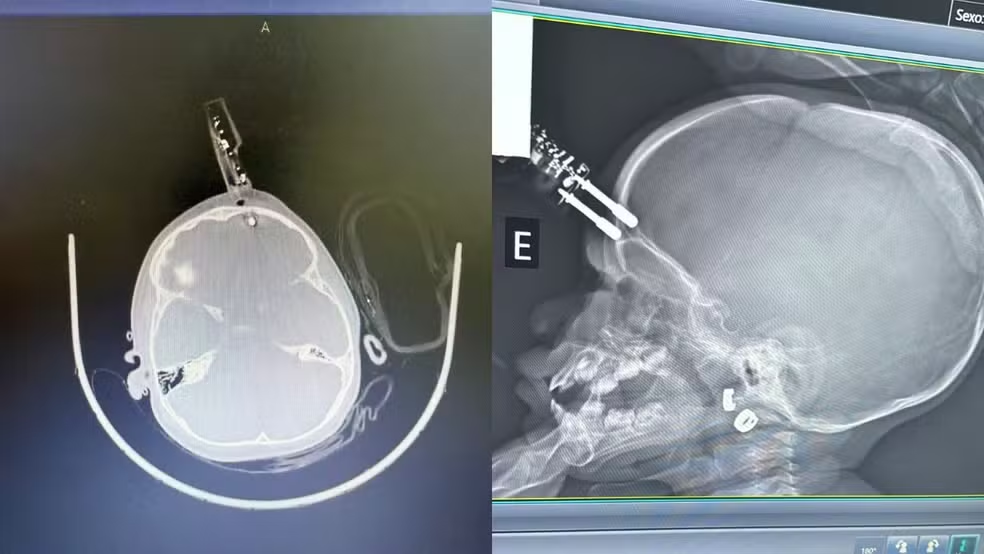

Uma menina de 1 ano, que sofreu um acidente ao cair da cama com um carregador de celular cravado na testa, recebeu alta hospitalar em Divinópolis (MG). O objeto perfurou o osso frontal e atingiu o cérebro, mas a criança já está em casa com a família.

A cirurgia de emergência foi feita rapidamente para remover o carregador, limpar e reconstruir a área afetada. O neurocirurgião responsável destacou que a rápida intervenção foi essencial para evitar complicações graves, como hemorragias e infecções. A menina segue tomando antibióticos e será acompanhada neurologicamente.